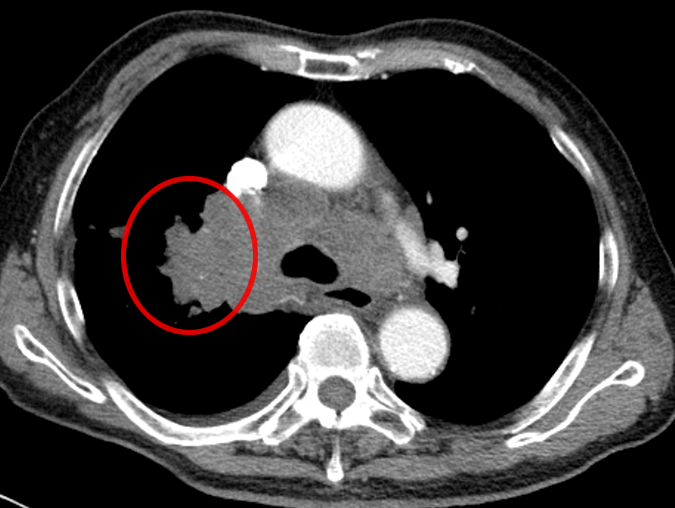

还有另一位患者,肺部结节只有 15mm,还合并了空洞,医生同样通过 CT 引导精准定位,成功完成经皮肺穿刺取到病理组织,最终诊断为 “腺癌”(免疫组化提示 CK7、TIF-1、NapsinA 阳性,排除其他类型肿瘤)。